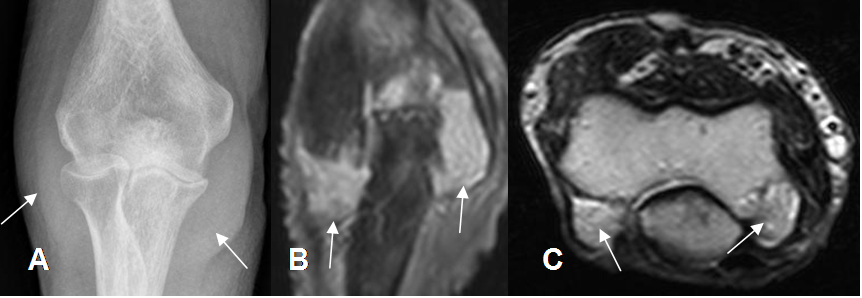

Fig 28. Artropatía reumática.

A: Rx AP. Osteopenia generalizada, con disminución de espacios articulares y prominencia de los tejidos blandos, a nivel bilateral. (Flechas).

B: RM coronal en STIR y C: RM axial en T2. Pannus hiperintenso en ambas secuencias, en la parte posterior de la articulación. (Flechas).